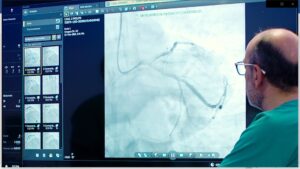

Dentro de la programación del Foro de Buenas Prácticas Salud Madrid se abordará, durante los meses de febrero y marzo, la actuación coordinada de todos los profesionales en la atención inicial al paciente con Síndrome Coronario Agudo (SCA), es decir, el CÓDIGO INFARTO MADRID.

Con esta práctica se pretende, por una parte, mejorar la atención urgente al paciente que sufre un SCACEST y además, reducir dentro de lo posible, los tiempos de acceso a la reperfusión en la CAM.